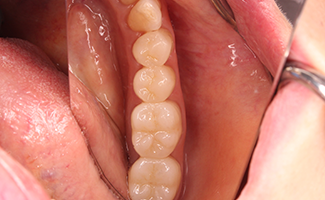

BEFORE

AFTER

高い審美性を持つ高品質樹脂でできた歯冠修復物です。天然歯より柔らかい材料なので、噛み合う他の歯を傷つけるなどの心配がないことが特徴です。基本的にダイレクトボンディング治療ができない比較的大きな虫歯が適応となります。